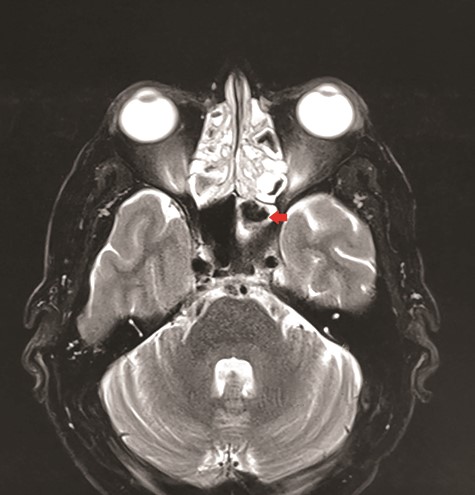

CT unveiled calcified densities within areas of hypoattenuation in the left sphenoid sinus. No marked bony destruction was observed (Fig. 2). A subsequent magnetic resonance imaging (MRI) was carried out to show hypodensity on T1 weighted post-contrast, and flow void in T2 weighted images within the same sinus (Figs. 3 and 4). Following informed consent, an emergency endoscopic left trans-ethmoidal sphenoidotomy was performed under general anaesthesia. A dense, darkened clay-like mass surrounded with the mucopurulent discharge was noticed within the left sphenoid sinus. The mucosa appeared inflamed and oedematous without clinical evidence of frank necrosis. The debris was utterly removed with a curette and sent for evaluation. The left sphenoid sinus was widened and thoroughly rinsed.

Axial view of MRI T2 weighted revealed flow void signal within the left sphenoid sinus.